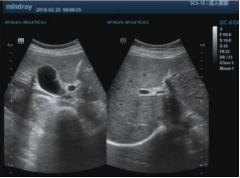

圖爲龍女(nǚ)士治療前與治療後對比照(zhào)

住院的77天裏,龍女(nǚ)士經曆了從病重、病危、病重、平穩的波折,可(kě)謂九死一生(shēng)。期間,一直守在龍女(nǚ)士身(shēn)邊的16歲小女(nǚ)兒,休學陪伴照(zhào)顧,“老公要回去(qù)管家裏的田地啊,不然醫藥費都(dōu)湊不齊了。小女(nǚ)兒不放(fàng)心我一個人在醫院,堅持停課來照(zhào)顧我。”如(rú)今經過五周期規範化療,龍女(nǚ)士的病情已完全緩解。